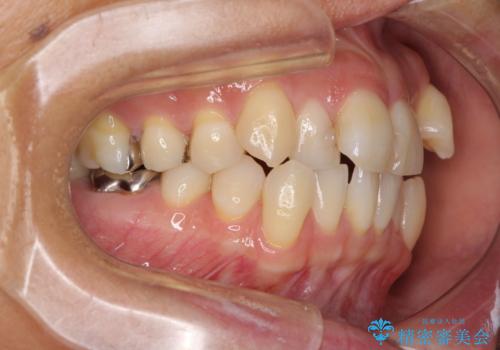

- 八重歯と、それによる口元の膨らみを気にして来院された患者様です。

八重歯・デコボコの解消とともに、前方に張り出した上顎前歯を引っ込めることを目的とし、上下左右の第一小臼歯4歯を抜歯をしてワイヤー矯正により治療することとしました。